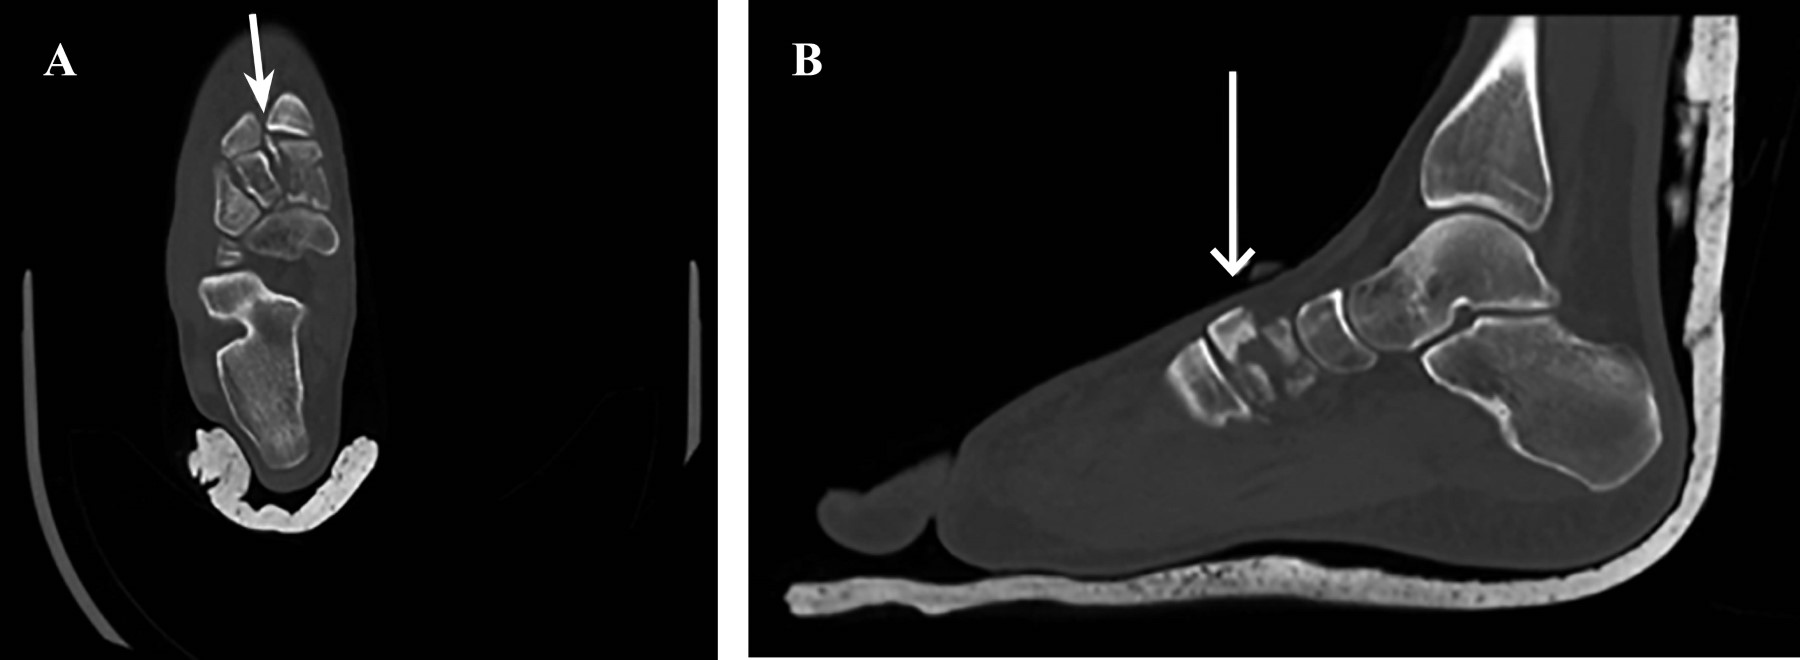

Figure 3